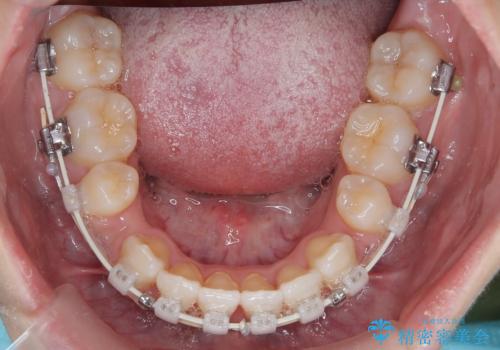

- 矯正装置

- 審美装置

左側犬歯が埋伏していましたが、第一小臼歯(4番目の歯)を抜歯したことでできたスペースに牽引し、右側の飛び出した八重歯を含め、歯全体を整列することができ患者様も満足していただきました。

犬歯牽引を行うかはCTを撮影し判断を行なっています。